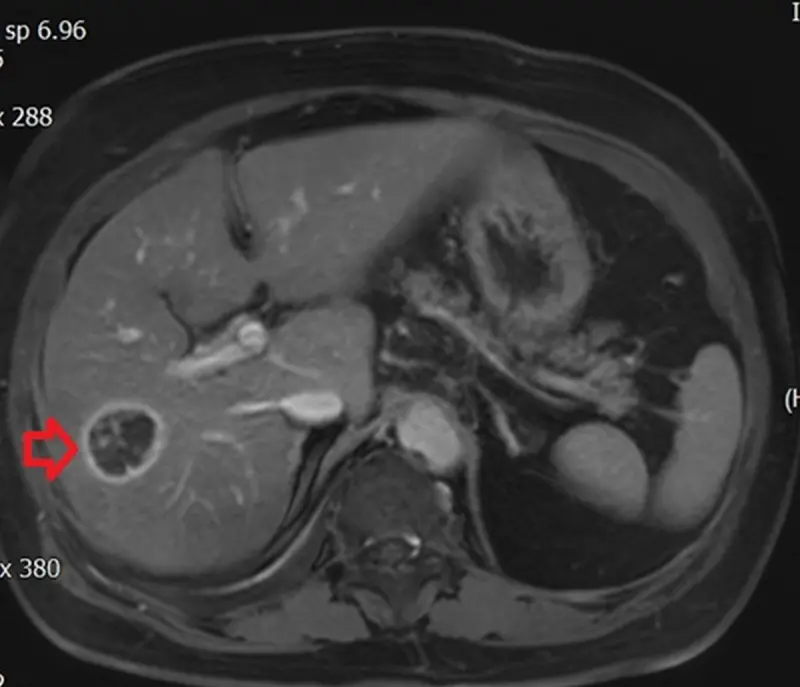

陳泓達表示,經電腦斷層、核磁共振檢查後,確診許女士罹患肝癌,隨即規劃治療方案,考量她的體力與肝功能等,決定採行射頻燒灼術,先利用超音波定位,再以電燒針穿刺腫瘤中心,透過高溫誅殺癌細胞,治療過程僅需數十分鐘,對身體影響較小,有助術後迅速恢復。

陳泓達指出,目前治療肝癌除開腹手術、腹腔鏡與達文西手術外,對於腫瘤小、手術風險較高的患者,射頻燒灼術是有效且安全的替代方案;以許女士為例,經多科團隊會診並與家屬溝通後,確認這是最符合她身體條件的治療方式,結果也成功控制病情。